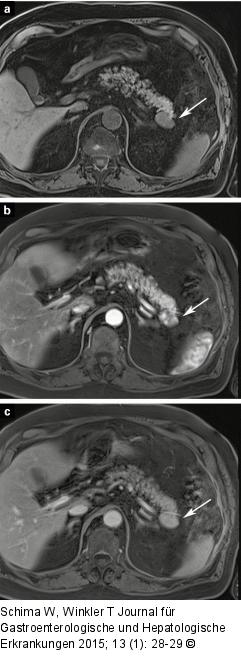

Abbildung 2a-c: Intrapankreatische Nebenmilz Die MRT nativ und nach Kontrastmittel zeigt ein Anfärbeverhalten der Läsion (Pfeil) wie das der Milz (lateral davon gelegen). |

Die MRT nativ und nach Kontrastmittel zeigt ein Anfärbeverhalten der Läsion (Pfeil) wie das der Milz (lateral davon gelegen). |